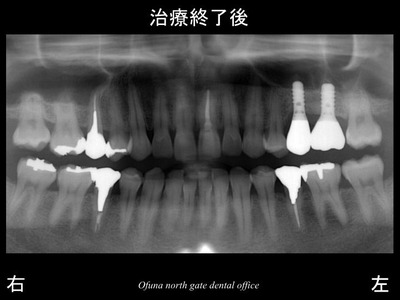

以下は、インプラント治療が終了した後です。

ここで見ていただきたいのが、インプラントの太さです。

奥歯ですので、欠損部の幅は、当然のことながら前歯より幅が広いですし、

歯の大きさも違います。

天然歯に近い被せ物の大きき、

インプラントの太さ

となっているのです。

以下はインプラント治療が終了した後です。

先ほどの症例と違うのは、

インプラントの太さ、

被せ物の大きさです。

これは、欠損部の幅に合わせたのです。

以下は、インプラント治療が終了した後のレントゲンです。